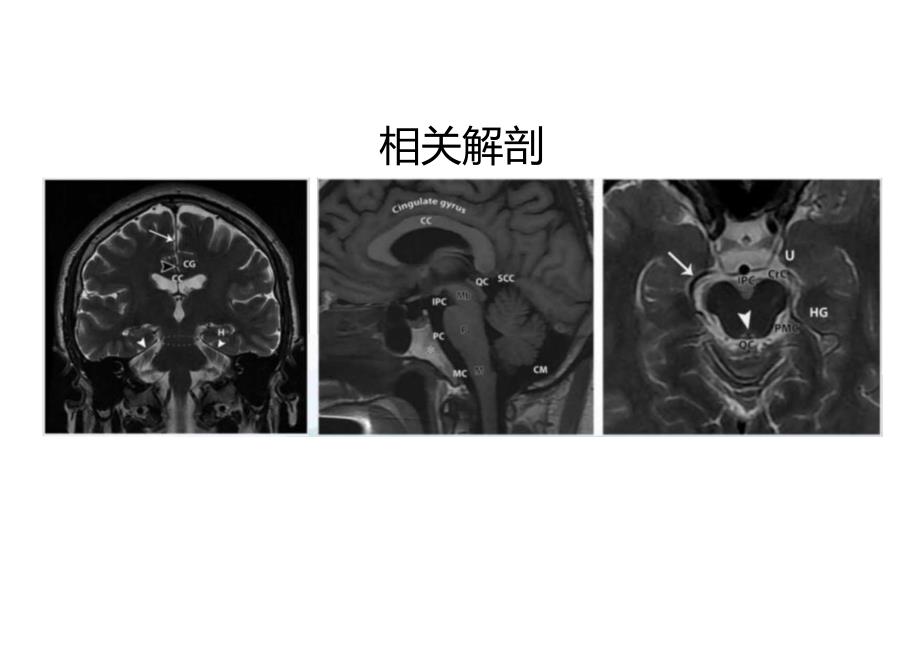

1、脑疝的影像诊断概述 定义:脑组织从正常位置移位到邻近间隙,是一种危及生命的疾病。 脑疝可产生脑损伤,压迫颅神经和血管引起出血或缺血,或阻碍脑脊液的正常循环,产生脑积水。 由于其位置,每种类型脑疝可能与特定的神经综合征有关。 病因:外伤性、血管性、肿瘤性、感染性、医源性因素、颅内低压。相关解剖分类小脑幕正中疝-下行性小脑幕疝-前疝:颠叶钩回疝1.侧疝-上行性小脑幕疝后疝:海马旁回疝颅外疝大脑镰下疝脑疝一小脑幕裂孔疝-一颅内疝一小脑扁桃体疝1.蝶骨峭疝ExtTMranUIhem脑疝综合征的诊断方法临床信息 解剖标志 组织移位方向 发生部位 间接征象 脑疝相关并发症Herniation-relate